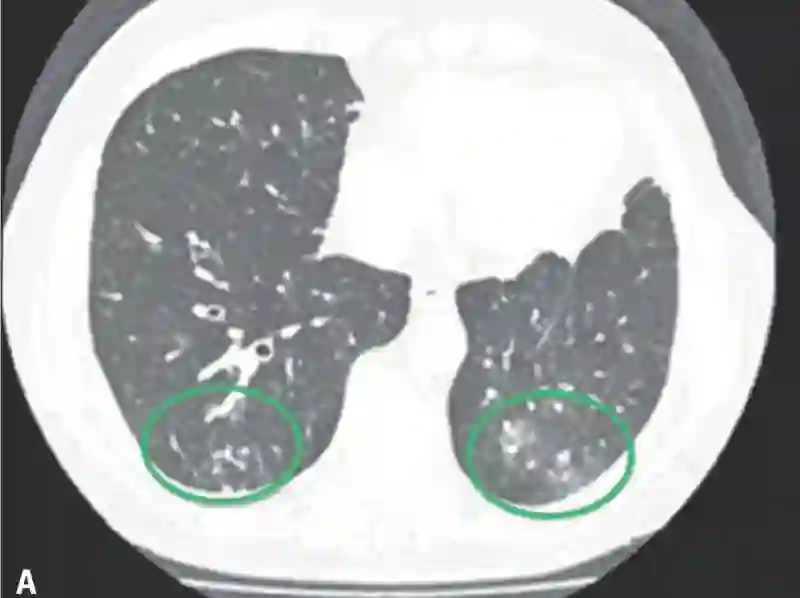

患者是一名81岁的老年男性,身患ⅢA期难治性肺腺癌。病人在进行手术治疗后又接受了放疗和卡铂+培美曲塞的辅助化疗。在随访4个月后,病人的病情出现了局部复发,在放疗治疗无效后,病人又接受了卡铂和紫杉醇的姑息性化疗,但是其病情并未得到有效的控制。同样,病人在传统治疗无效后选择了帕博利珠单抗每3周2mg/kg的免疫治疗方案。在治疗4个疗程后,病人开始出现呼吸困难和干咳,血氧饱和度也降至80%。CT检查显示双侧肺部出现弥漫性浸润灶,血常规检查显示其白细胞计数增高。所幸的是,病人在对症使用甲基强的松龙2mg/kg和抗生素治疗后,其肺部炎症得到了比较好的控制。

在本次报道的5名病人中,仅有一人为5级不良反应,并最终去世。其他4名病人均为3级不良反应,在接受糖皮质激素治疗后病情都有改善。大多数病人的CT表现肺部的磨玻璃样改变,早期临床表现为咳嗽和呼吸困难,不论对于病人还是医务工作者来说,免疫性肺炎的早诊断和早治疗都尤为重要,以上报道的病人中,有几人就是因为早诊断早治疗,在很短的时间内肺炎症状就得到了快速的缓解,因此我们说:肺炎不可怕,“早”字是关键。